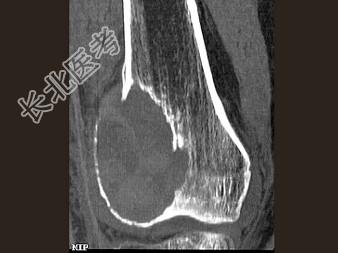

- 单项选择题男,24岁, 左大腿及膝部痛,结合图像, 最可能的诊断是 ( )

A、骨巨细胞瘤

B、骨囊肿

C、成软骨细胞瘤

D、动脉瘤样骨囊肿

E、骨肉瘤